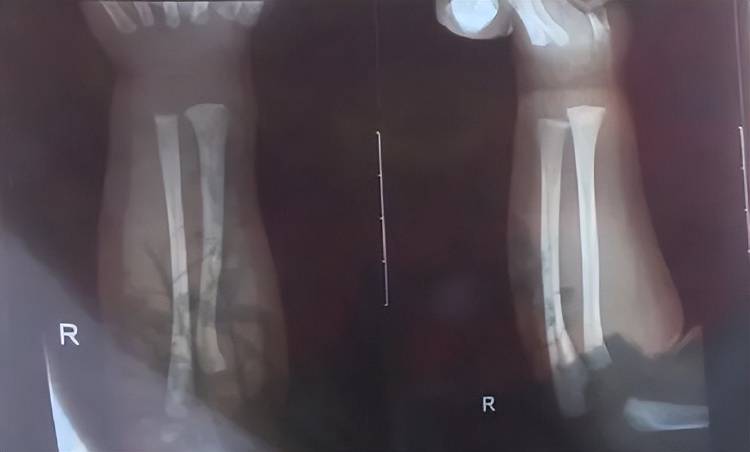

次日上午,孩子被带到附近医院检查,医生诊断发现他右手有两处骨折,第一处为右侧尺骨远端骨折,第二处为右侧桡骨远端骨折,随后医生给他做了石膏固定,“没想到,几天后孩子还被诊断出脑电图异常,医生建议复查水果虚拟币。”

孩子被诊断发现两处骨折